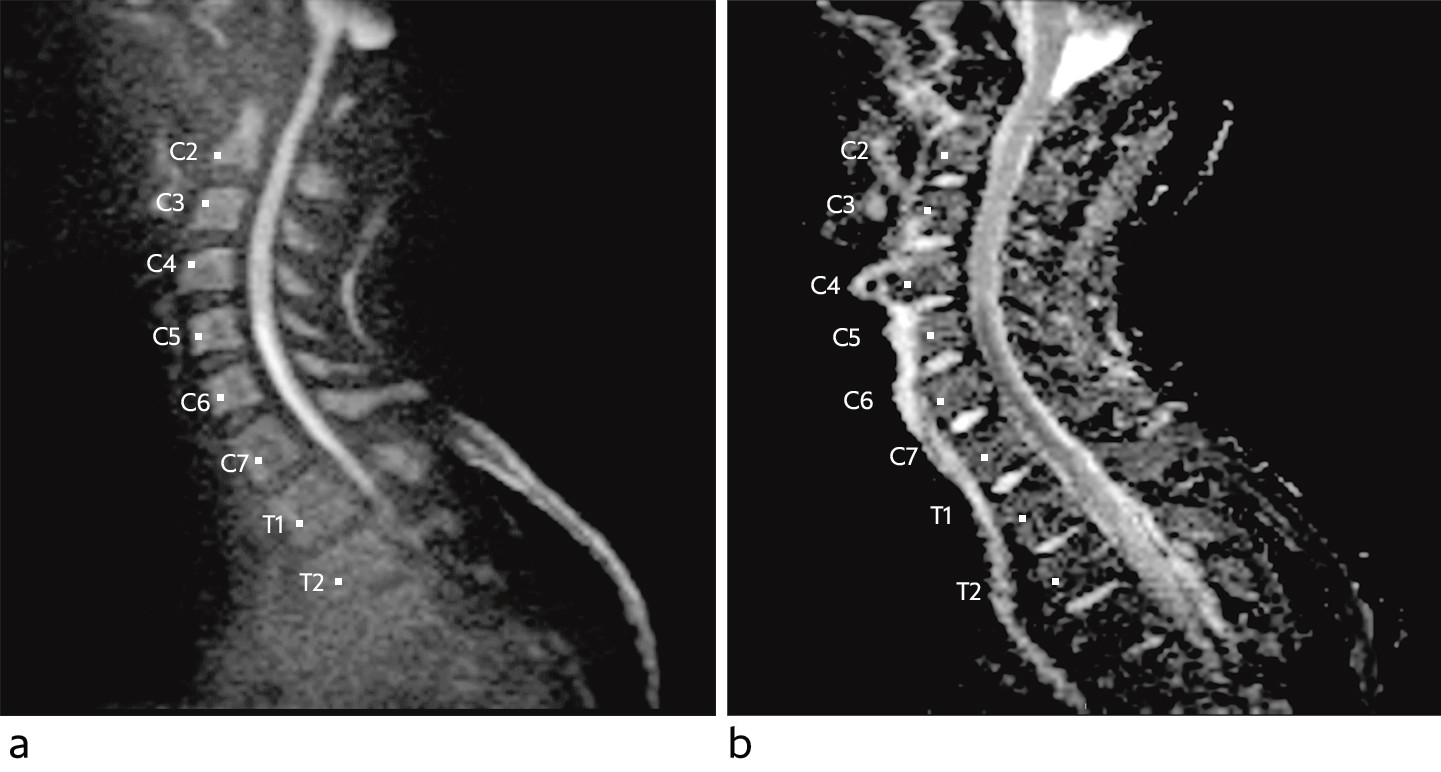

MR-undersøkelsen viste lav diffusjon ventralt i medulla fra nivå C5–Th1, utbredelse på nesten 7 cm (figur 1). Medulla var ikke svullen, og det ble ikke påvist kontrastopptak. På aksiale snitt (figur 2) var det i samme nivåer økt T2-signal i fremre horn bilateralt, såkalt slangeøyneutseende, forenlig med ett av de kjente mønstrene ved iskemi i forsyningsområdet til a. spinalis anterior. Funn med lav diffusjon med «vaskulær distribusjon» gav mistanke om cytotoksisk ødem på bakgrunn av fersk iskemisk skade. På dette tidspunktet var det ingen holdepunkter for infeksjon, da pasienten var afebril og hadde normale funn på blodprøver. Inflammasjon var fortsatt en mulig differensialdiagnose. Det var ingen signalavvik eller holdepunkter for infarkt eller annen patologi i cervikale virvelcorpora, men noe dehydrerte skiver. Senere samme dag ble det supplert med CT totalaorta, som ikke avdekket disseksjon, aneurismer eller annen embolikilde.